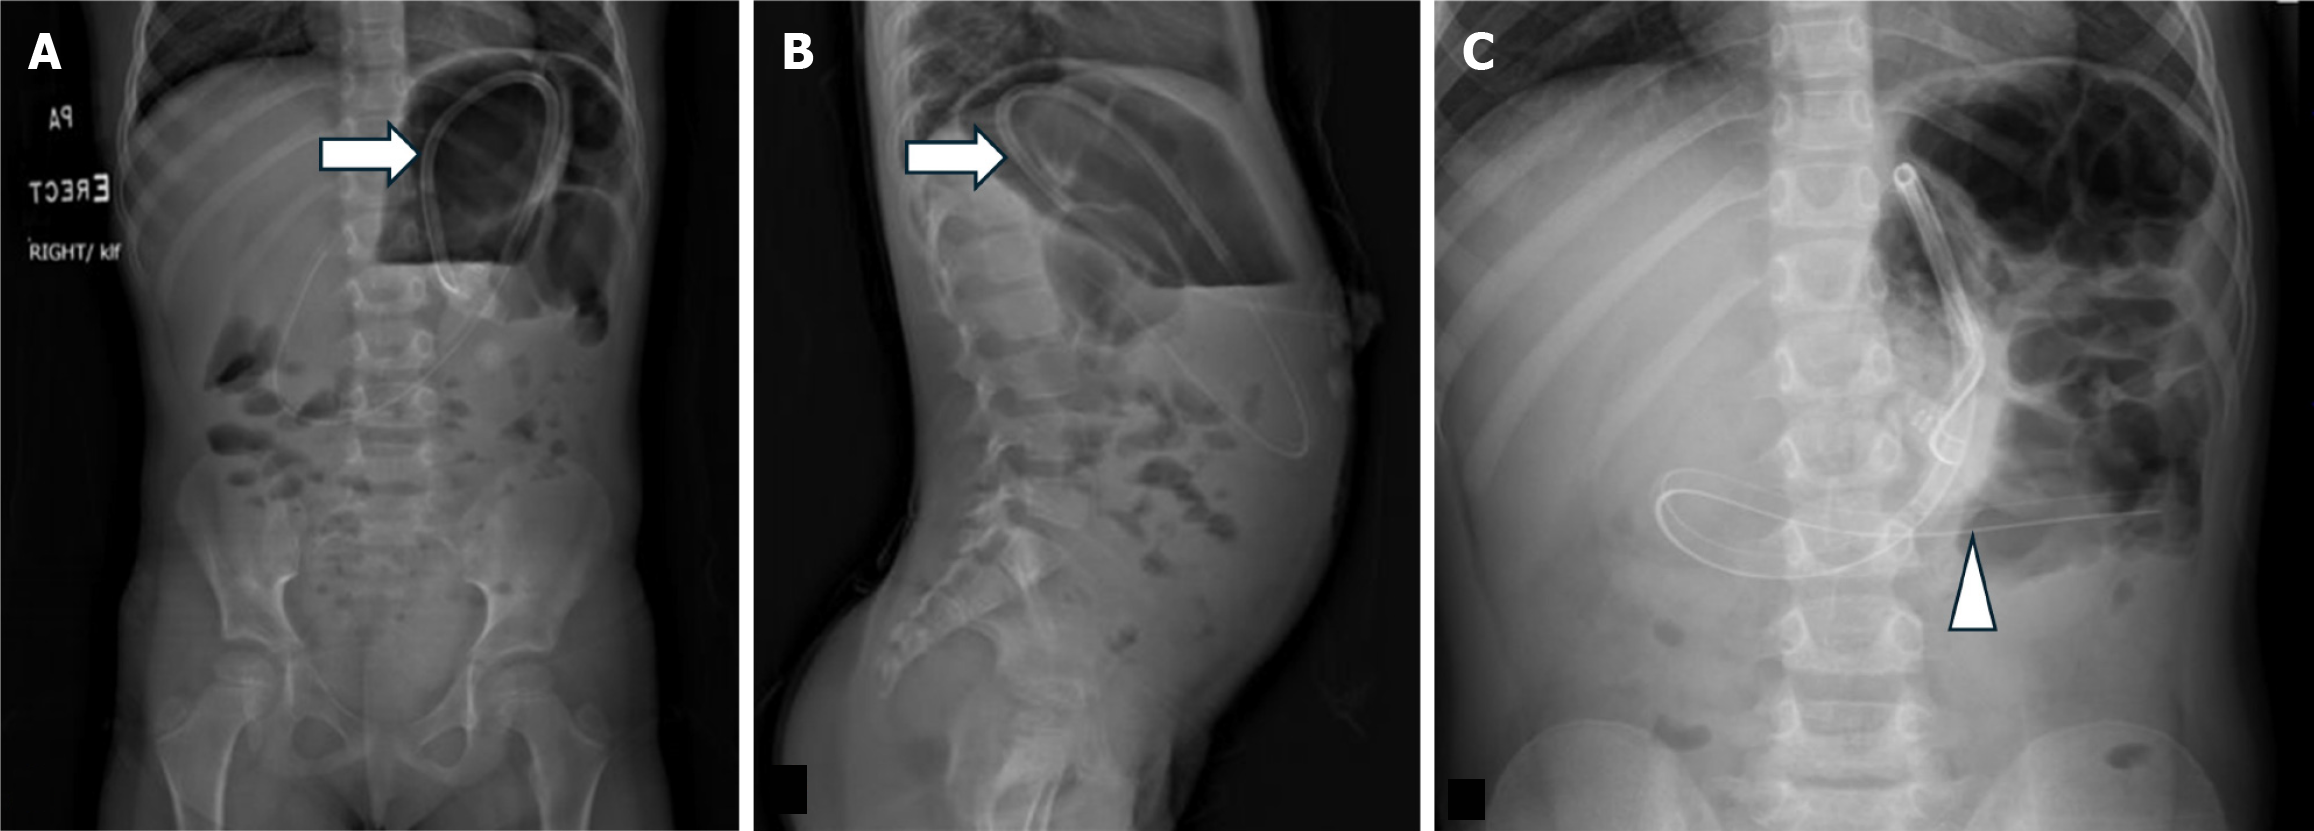

Figure 5 Gastric outlet obstruction secondary to gastrostomy tube ballon.

A: Frontal; B: Lateral. A 2 year old presented with increased abdominal distension, gagging and reflux from gastrostomy tube (G-tube). Portable radiographs, frontal and lateral after contrast administration revealed retention of contrast in an overdistended stomach (arrowhead) with the G-tube balloon in the distal stomach (arrow). Obstruction was later relieved after the balloon (arrow) was deflated and the tube was exchanged.